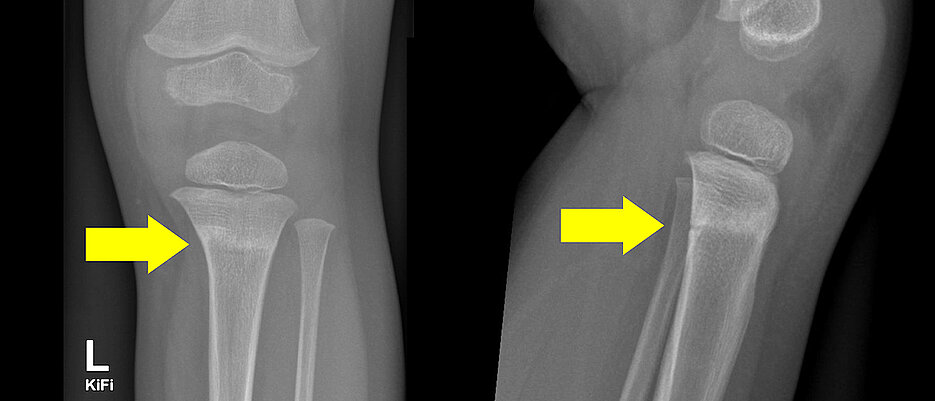

Zu den „klassischen“ Verletzungen von Kindern unter sechs Jahren beim Trampolinspringen gehört die proximale Tibiafraktur, also ein Bruch des oberen Schienbeins. „Dafür hat sich in der Fachwelt schon der Name ‚Trampolinfraktur‘ eingebürgert“, sagt Professor Meyer. „Ursächlich ist hier immer das Trampolinspringen zusammen mit einem schwereren Kind oder einem Erwachsenen. Hier kann es leicht zu einem Katapult-Effekt kommen“, so der Mediziner.